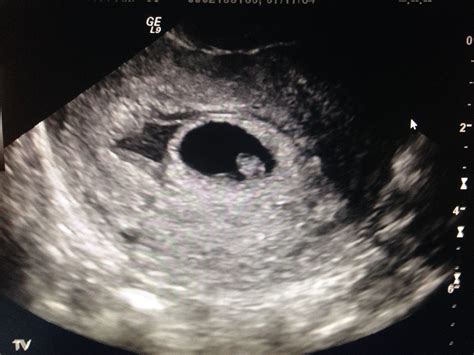

• Transvaginal Ultrasound: This is the gold standard for diagnosing a subchorionic hematoma. The imaging allows the doctor to visualize the size and location of the blood clot relative to the gestational sac.

• subchorionic hematoma pregnancy pictures